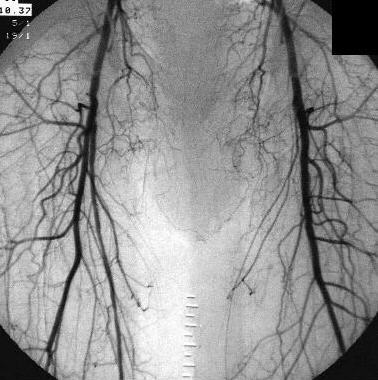

the pathological image-left and the physiological image-right

Adult man, 63-years-old,

admitted with pain in the left leg. Physical examination reveals gangrene at

the left foot

Peripheral vasclar

disease with occlusion of the superficial femoral artery at the left side caused

by atherosclerosis.